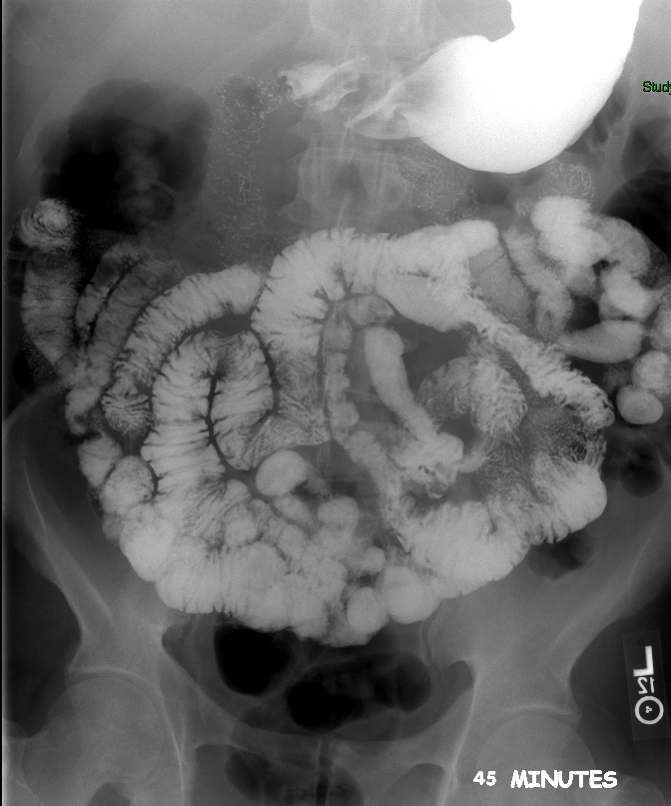

- Once 15 minutes has passed since the patient drank the barium, the technologist will obtain a prone (if possible) radiograph

(key image 2).

- Prone positioning is preferred because while lying prone, the weight of the body provides compression of the bowel loops.

- The film should include the entire stomach as well as the bowel that is filled with contrast.

- The technologist will obtain radiographs at 30, 45, and 60 minutes after the initial administration of barium. If the column of contrast material has not reached the large bowel on the 60 minute film, the technologist will obtain images every 30 minutes until contrast can been seen in the cecum

(key image 3)

(key image 4)

(key image 5).